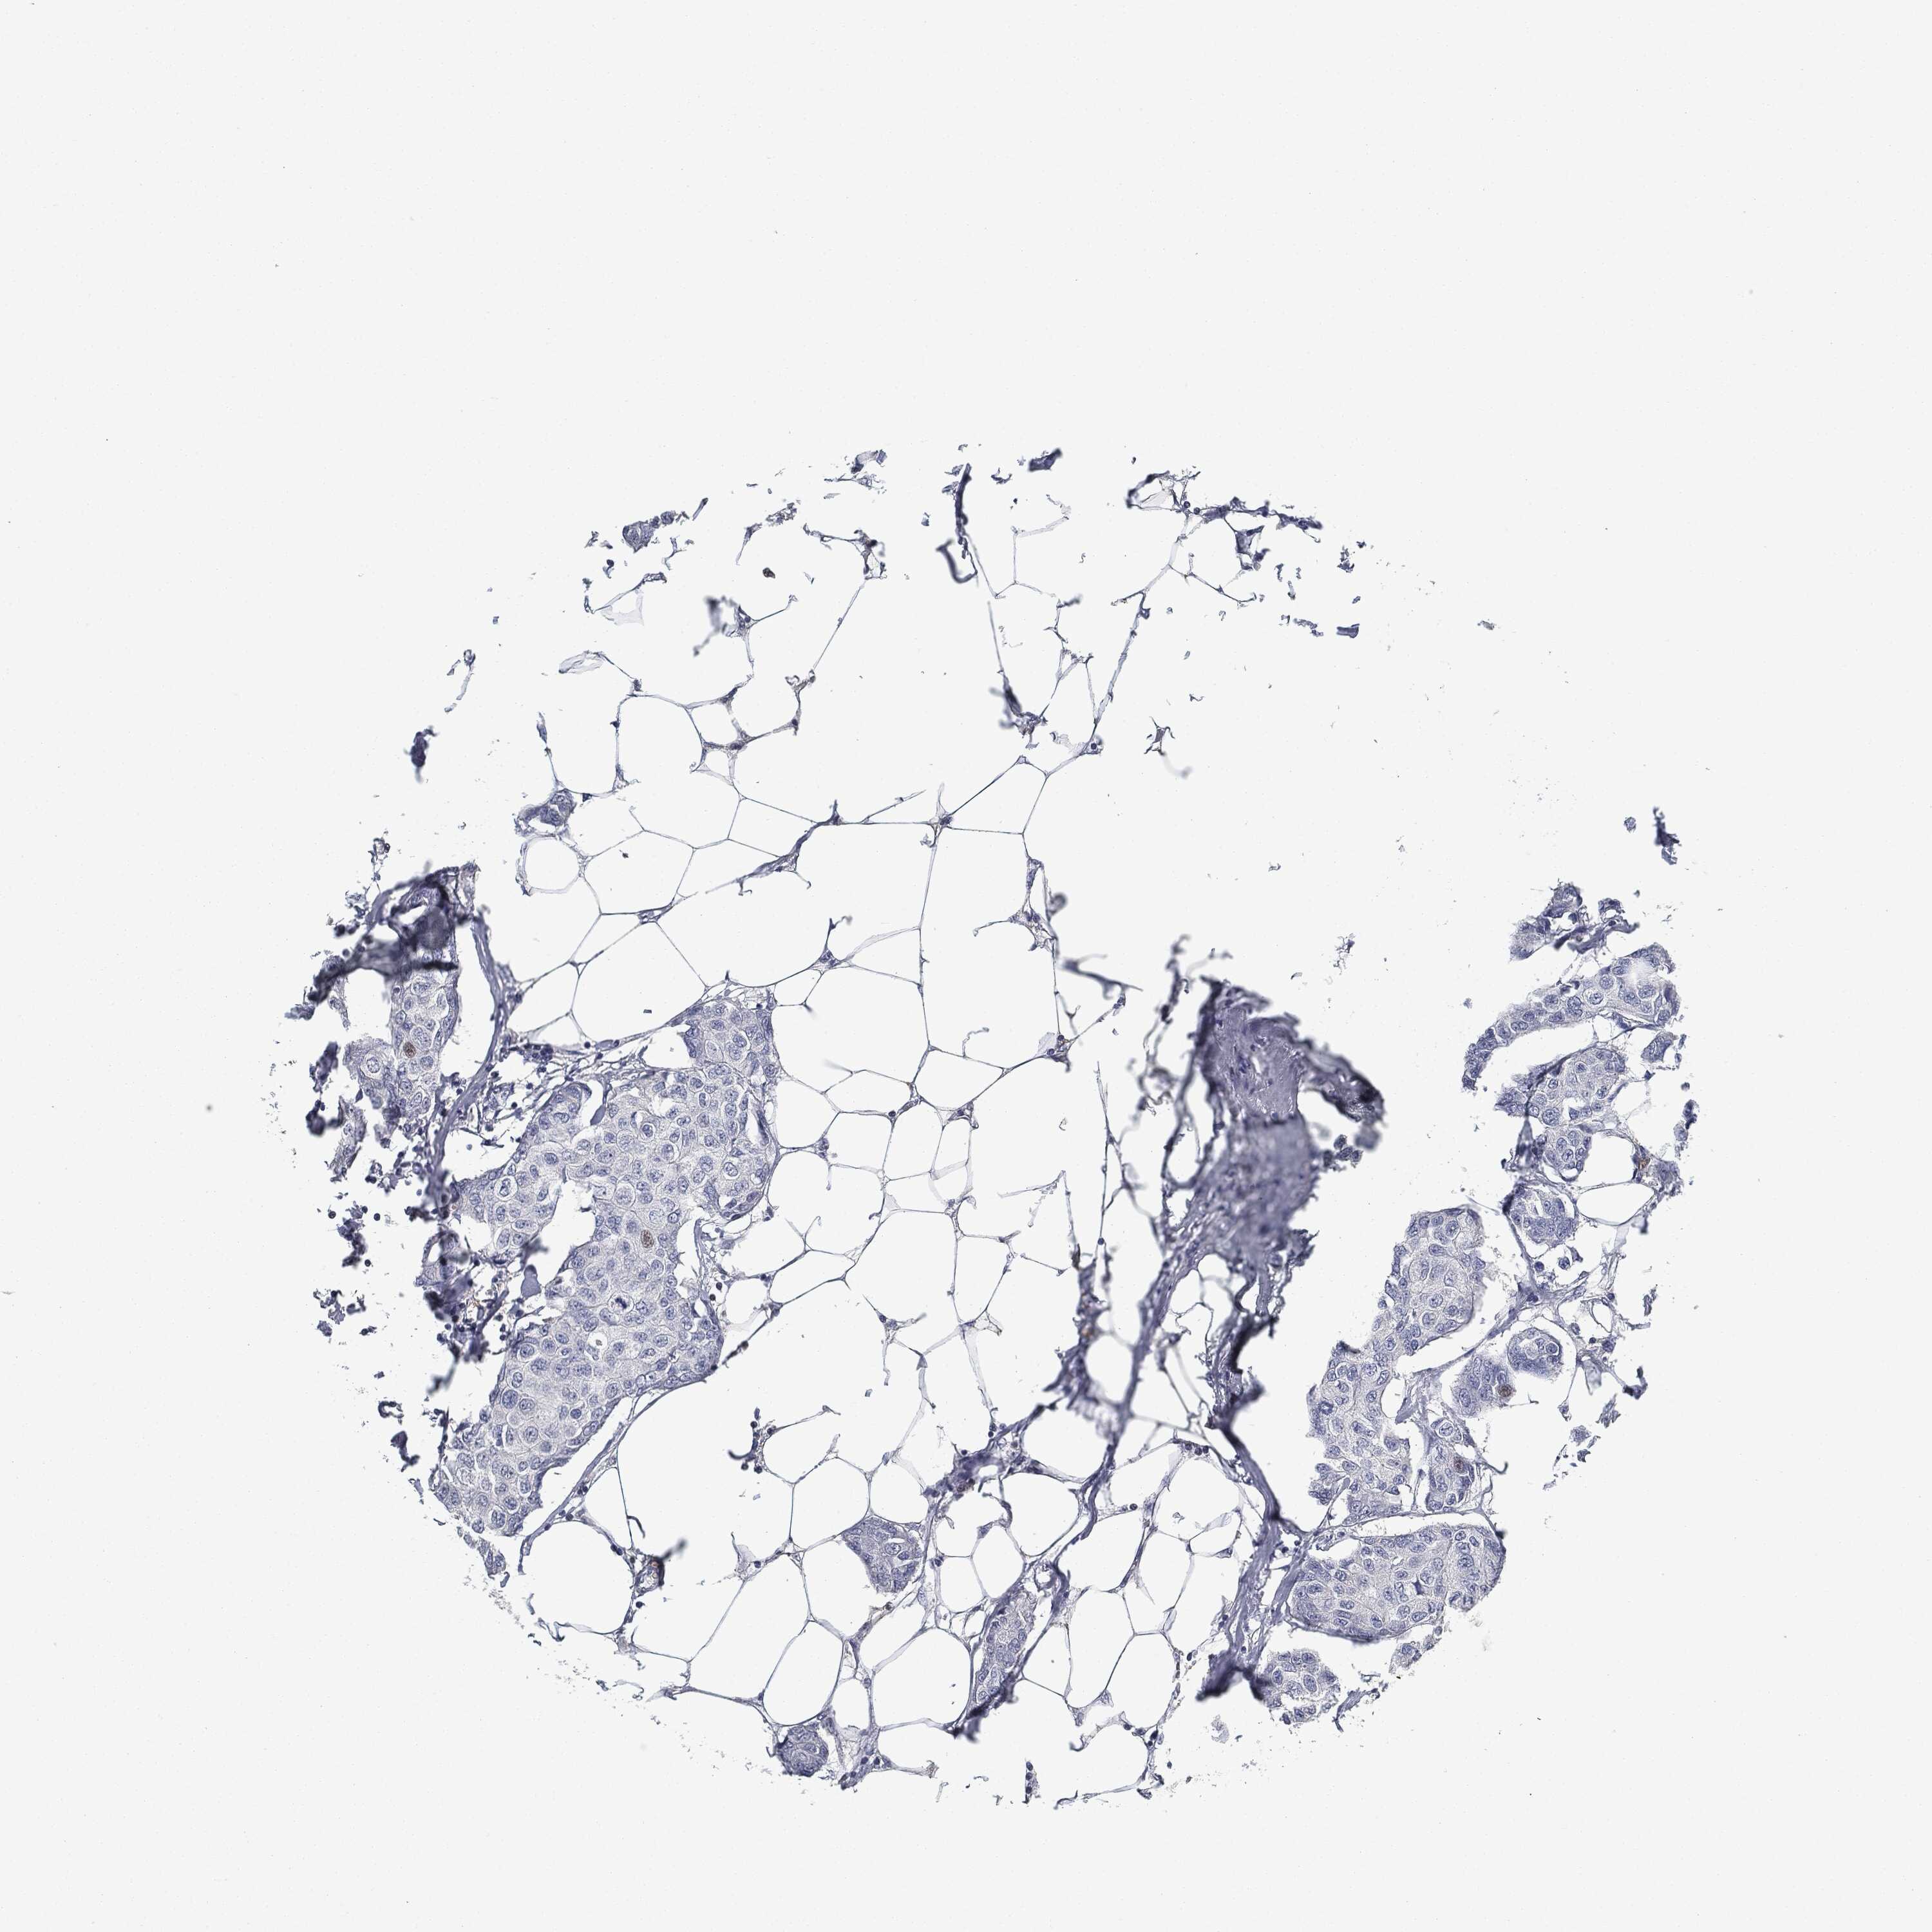

BRCA TCGA BRCA VALIDATION PROTEIN EXPRESSION

ANTIBODIES

AND

VALIDATION